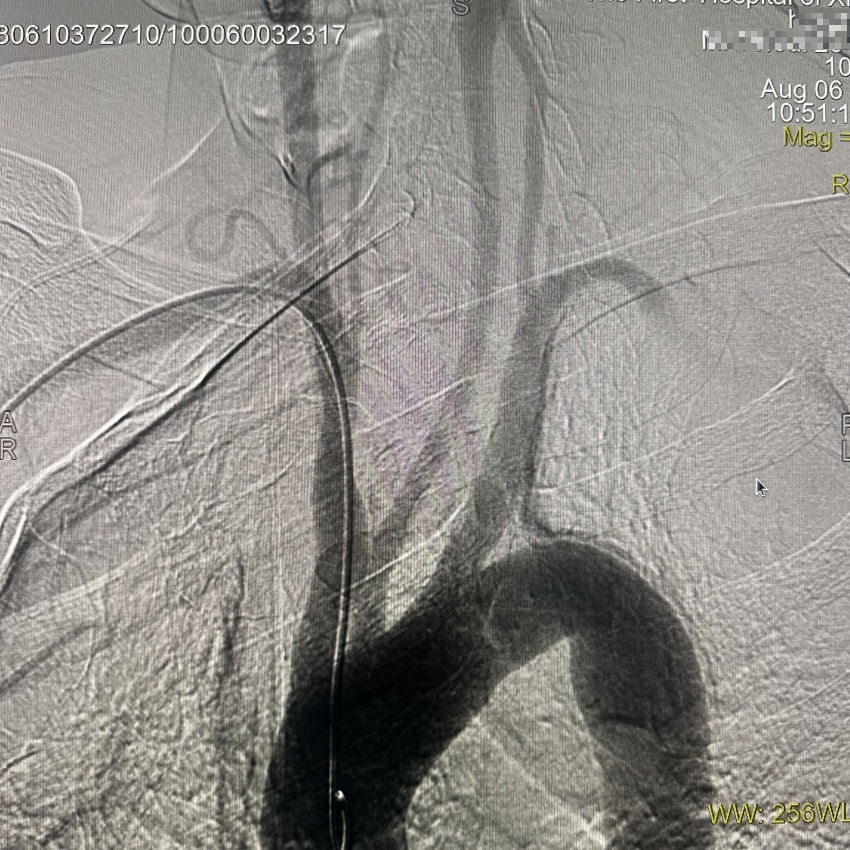

通路建立:患者主动脉弓造影显示Ⅲ型弓,病变为右侧大脑中动脉栓塞,故选择赛诺神畅APEX TRA GC™5F-130 SIM2导引导管同轴长鞘建立通路。

动脉长鞘怎么置入一技之“长”丨经桡及经股困难入路应用赛诺神畅APEX TRA GC™导引导管建立通路病例合集_https://www.jmylbn.com_新闻资讯_第7张

Ⅲ型弓